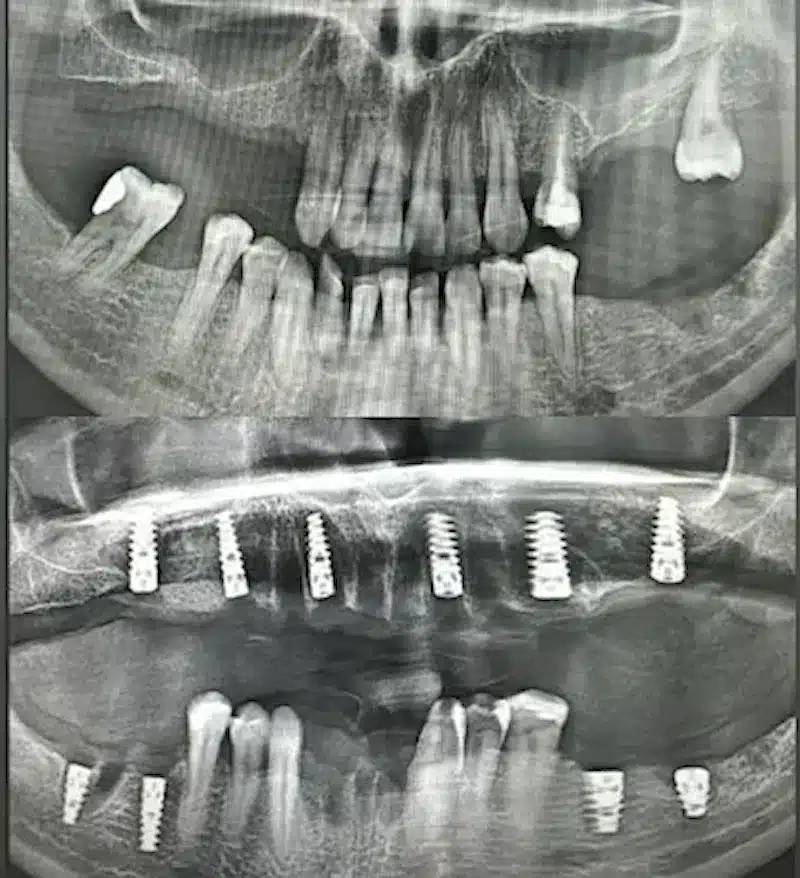

Dr. Seden Aksu is a specialist in modern implantology and surgical dentistry with extensive experience in the management of complex clinical cases. In her practice, she applies comprehensive surgical planning, minimally invasive techniques, and advanced regenerative technologies aimed at restoring both the function of the dentoalveolar system and the aesthetics of the smile. Dr. Aksu has significant experience in performing implant procedures, bone augmentation, and periodontal surgery, including the treatment of patients with severe bone loss. The primary goal of her work is to achieve stable, long-term outcomes in implant rehabilitation and the restoration of oral tissue health.